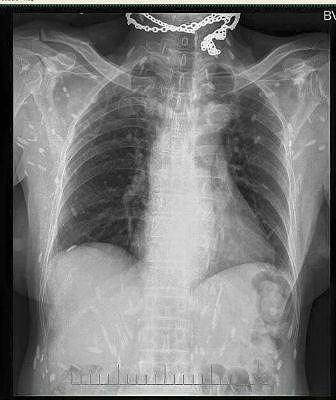

_ Dấu hiệu khi nhiễm sán heo là khi trẻ đi tiêu, sán sẽ tự đi ra theo đường phân hoặc trẻ bị sụt cân, suy dinh dưỡng. Trường hợp nguy hiểm hơn, sán lợn có thể "lạc" lên não làm trẻ co giật, hôn mê, nổi sần trên da thì nên đưa trẻ đến bệnh viện thăm khám và xét nghiệm.

_ Thông thường, bệnh nhân có dấu hiệu ký sinh trùng xuất hiện ở da như nổi sần, hôn mê, co giật, yếu liệt chi... Bác sĩ nghi ngờ do ký sinh trùng hoặc những bệnh lý liên quan khác đều cho xét nghiệm tìm ký sinh trùng.